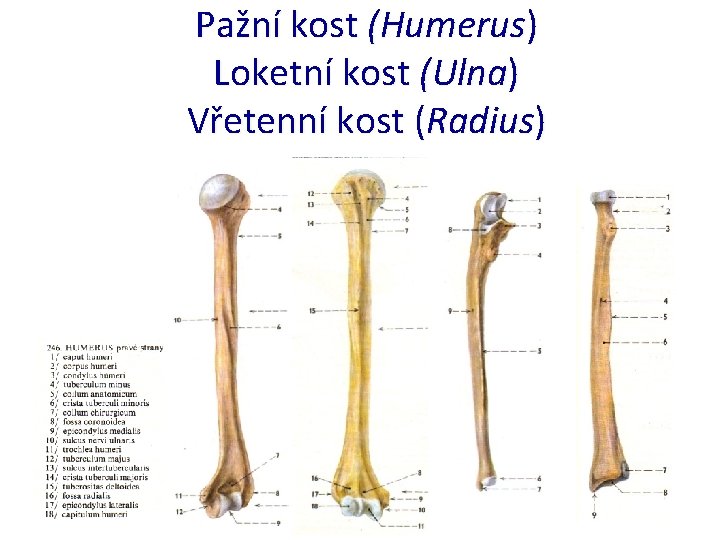

Pažní kost (Humerus) Loketní kost (Ulna) Vřetenní kost (Radius)